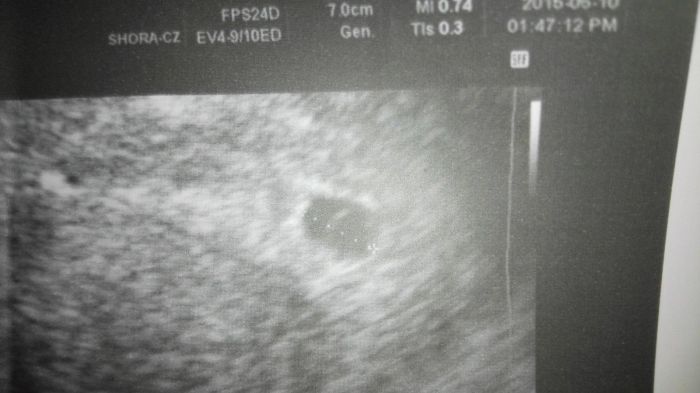

Holky ahoj chci se zeptat 5 dní mám nového gynekologa, protože jsme se stěhovali zjištěno bylo TT poslední ms 1.5 plus mínus 2 dny. 1.6 hcg 340 4.6 850 první foto v ten den 860 hcg po té krev brána nebyla další středu jsem šla k dr s tím, že sem trošku zakrvácela, jak sem byla na wc na velké hned nasadil ustrogestan a ještě něco.V pondělí 15.6 jsem šla znovu k němu s tím, že je mi dobře at se koukne hned mě poslal do nemocnice na hcg a utz, tam mi dr, č 1 řekl, že nemá důvod mě tam hospitalizovat, že vezmeme jen krev a uvidíme vše, tam je kromě plodu váček roste. 19.6 jsem šla znova na utz a hcg byl tam jiný doktor č 2 řel že hcg je normální a zatím bez plodku jinalk v pátek další odběr no dnes jsem, tam přišla s šokem, že je tam můj gynekolog co mi řekl je, to co tu dělám ještě od pondělka, že sem měla být v nemocnici atd udělal utz a řekl, že to bude mimo dělohu, protože krev jde pomalu nahoru jen o cc 1500 a že mám něco u vaječníků na pravo a v děloze taky, že to je mimoděložní a, že tu musím ležet a hlídat než to praskne okolo tech 6000 hcg to praská a můžu vykrvácet. tak sem se ptala tedy jestli sem těhotná nebo co mám dělat a on, že jo ale kde to neví a ptala jsem se, jestli plod ještě může vylézt a on, že to je jako bych vyhrála s portku 1% letěla jsem domů že dnes nezůstanu- Hned jsem šli k jinému dr a on mi udělal utz, že mimodělohu to není, že to je v děloze ukazoval mi to na utz a, že to bude nejspíš cysta, tam že to někdy bývá na začátku. Jsem prý 5–6 týden něco mezi tím a v ůterý mým dojít na další hcg a utz a do té nemocnice jít nemám pokud náhodou se objeví silné bolesti a krvácení mám jít. Co si o tom mám myslet? Hodím sem foto co mi napsal můj gynekolog ke, ktrému už nejdu i foto co mám za 14 dní utz a váček nebo co to je měří 8.3 mm

foto je z min týdne zrpáva je od mého doktora od kterého sme dnes po vyslechnutí přesla a letela jinam